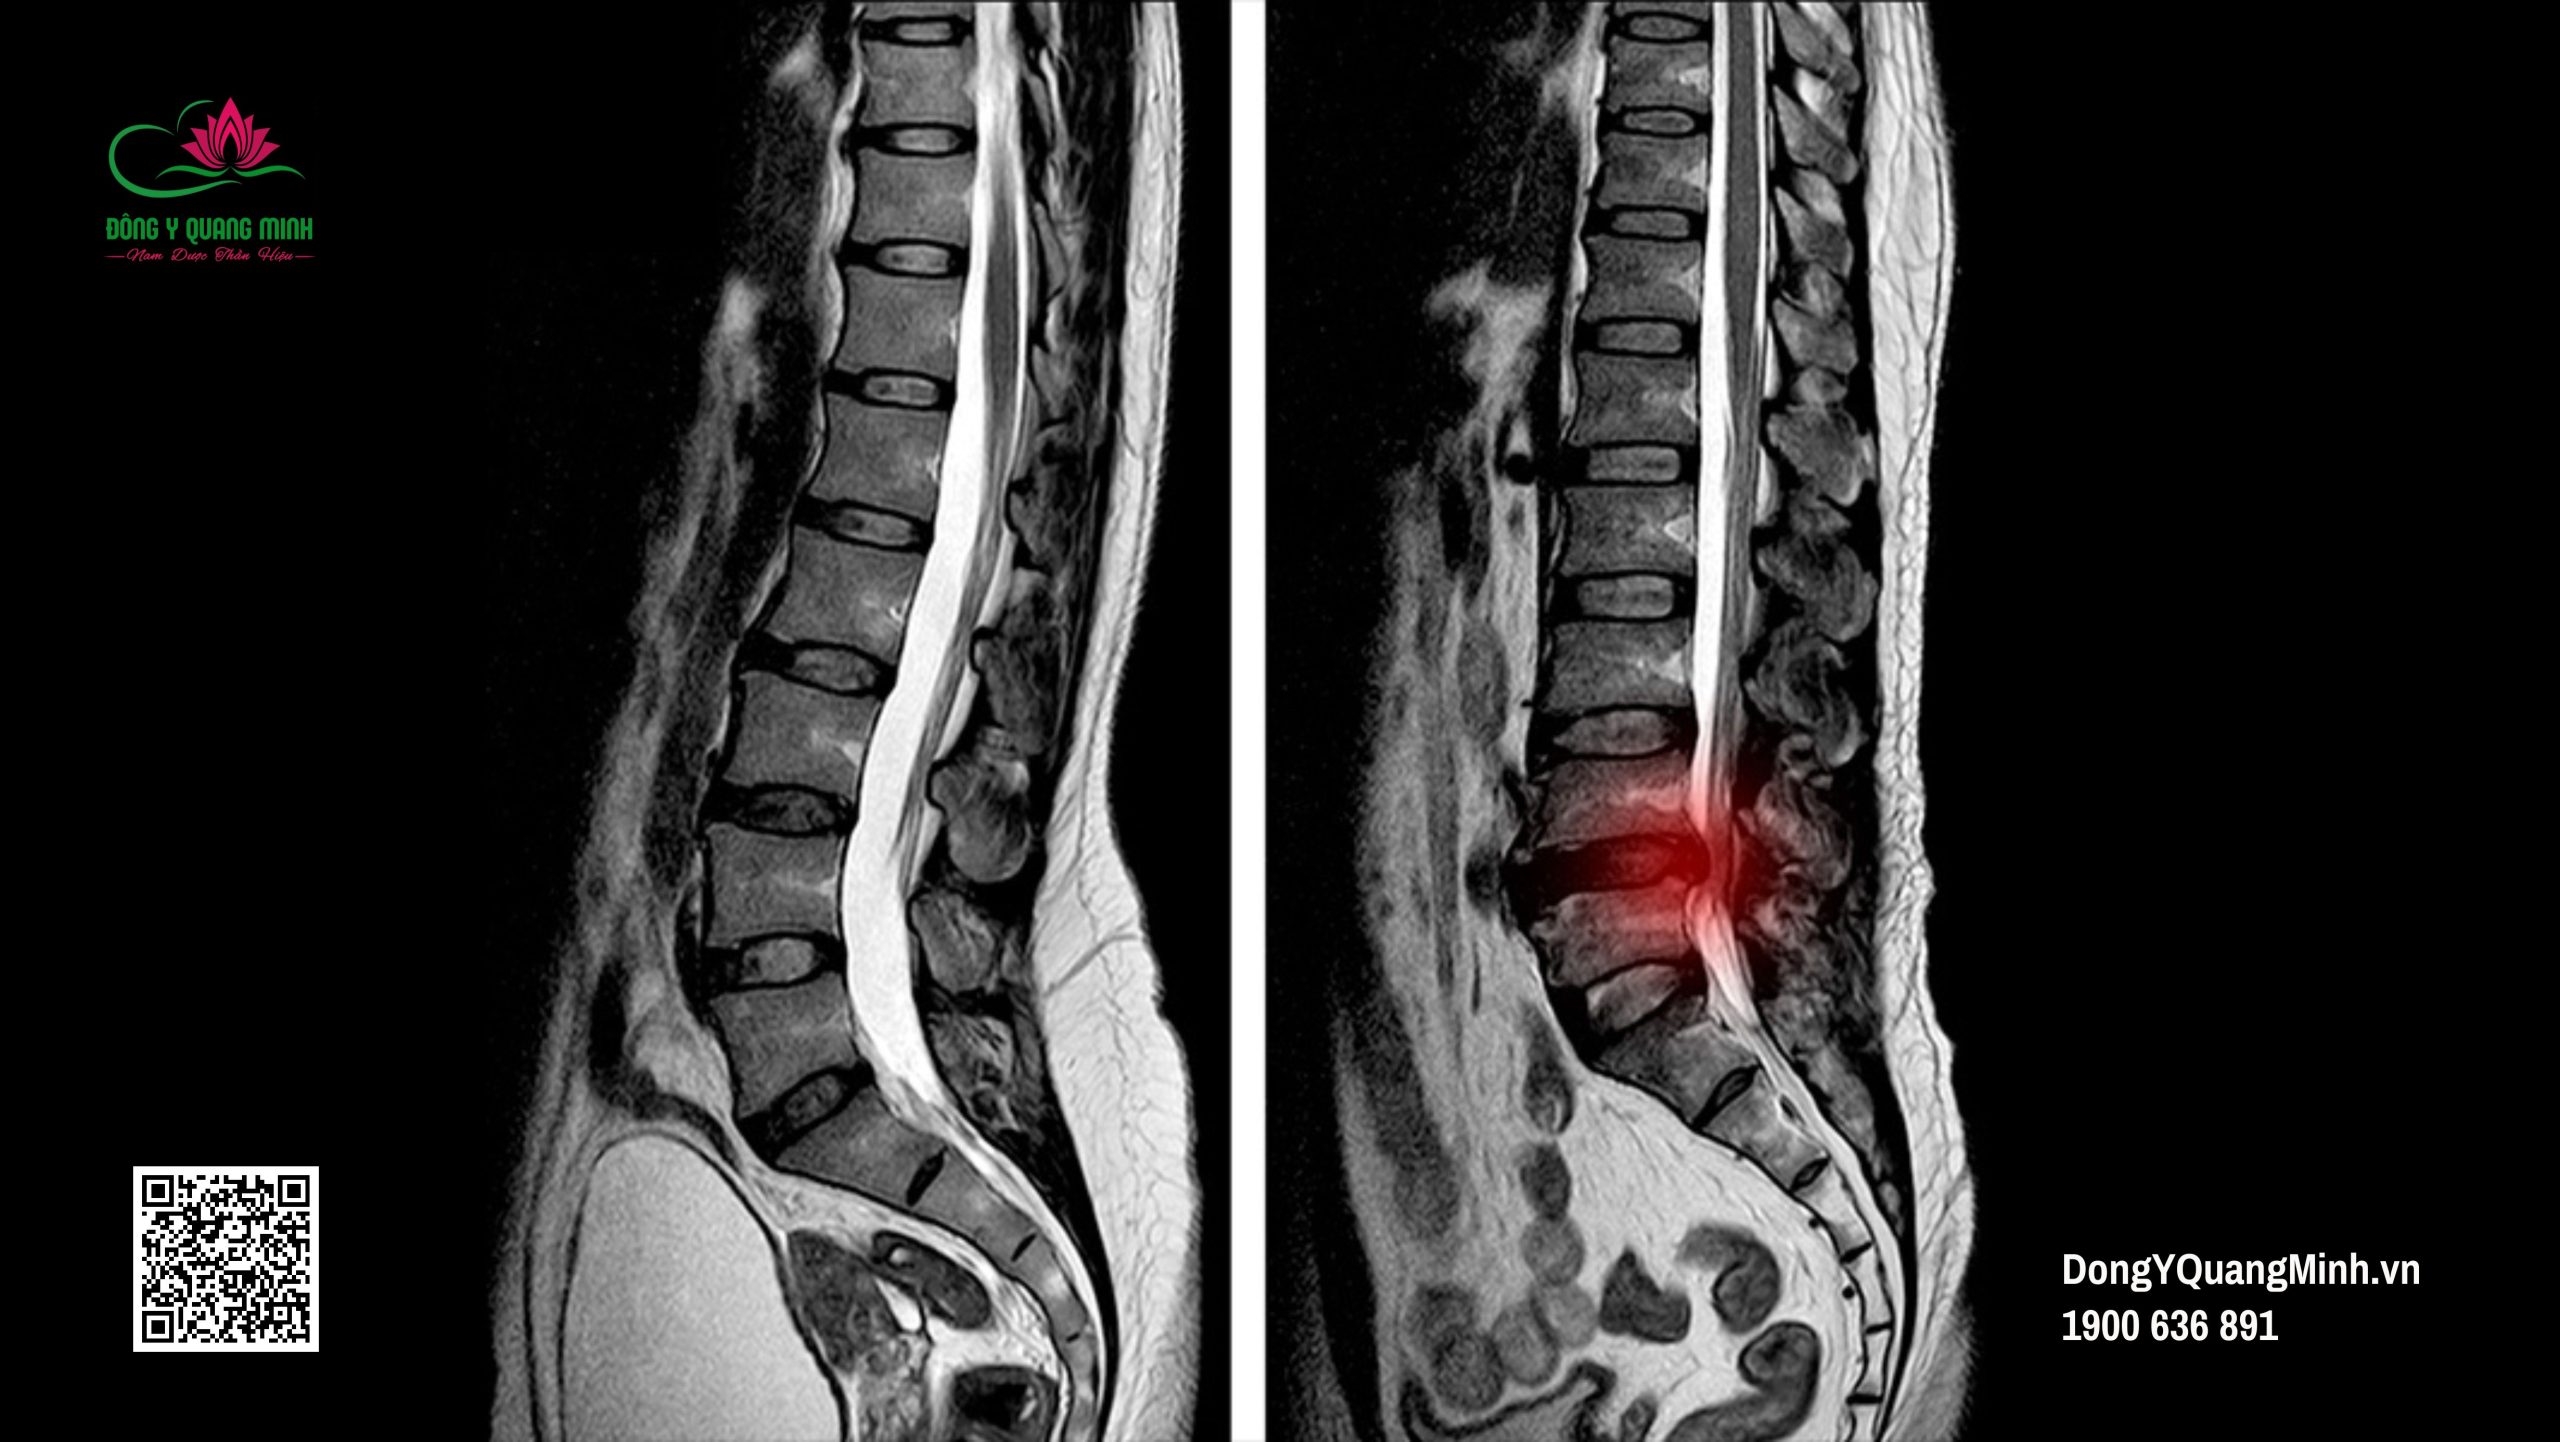

Thoát vị đĩa đệm cột sống thắt lưng là bệnh lý phổ biến trong cộng đồng, đặc biệt là ở những người trong độ tuổi lao động. Thoát vị đĩa đệm cột sống thắt lưng, hay được biết đến với tên Tiếng Anh là Lumbar Herniated Disc, là tình trạng nhân nhầy đĩa đệm đốt sống lưng thoát ra khỏi vị trí bình thường trong vỏ bao xơ, chèn ép vào ống sống hay các rễ dây thần kinh gây ra các cơn đau dữ dội, đau âm ỉ. Đặc biệt tình trạng thoát vị lưng hay xảy ra ở đĩa đệm L4L5 và L5S1.

Để chẩn đoán một bệnh nhân có mắc thoát vị đĩa đệm hay không, bác sĩ cột sống cần có phim chụp MRI để xác định mức độ chèn ép dây thần kinh.